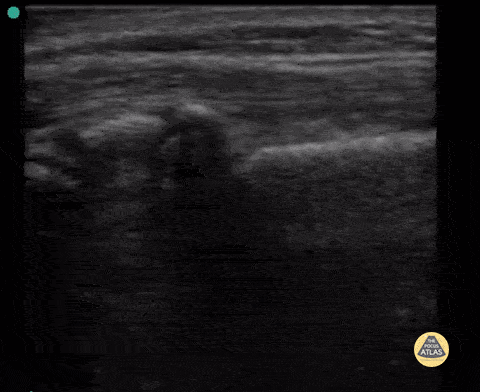

12 year old with SH-II fracture of distal radius. Not the abrupt metaphyseal angulation seen by ultrasound and physeal involvement. Contributor: Antonio Riera, MD